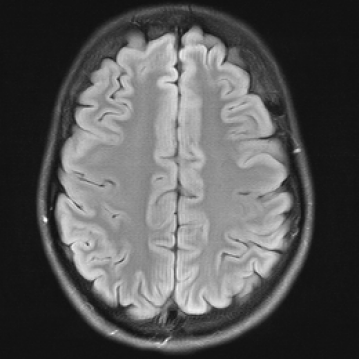

In Figure 1 we show a toy example of misjudgments that occur when evaluating the quality of a 2D MRI scan compared to degraded versions of the same image with standard measures. PSNR even yields the same value for all the very different degradations, and all of the standard measures fail in the judgement of massive local information loss (d), as well as in the judgment of stochastic noise (e) versus block artefacts (f). This toy example served as an inspiration to study the behavior of the standard measures in real life medical imaging tasks.

Figure 1: Illustrative toy example of problems occuring when using PSNR/SSIM/LPIPS for the evaluation of medical images in FR setting. Degradations have been added artificially to the reference (a) MRI scan: contrast enhancement (b), brightness change (c), hole (d), Gaussian White noise (e), jpeg compression (f). PSNR yields the same value for all degradations, SSIM and LPIPS fail to identify the hole (d), and misjudge the quality of (e) and (f).